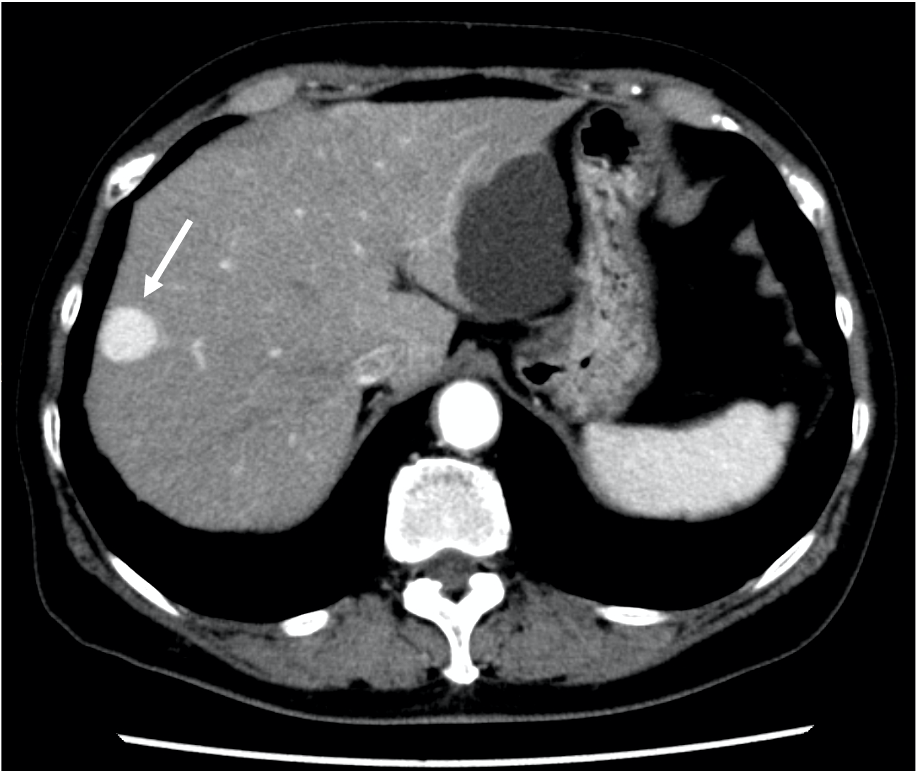

Amazon.com: EOB-MRI/Sonazoid 超音波による肝癌の診断と治療